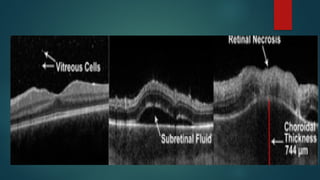

4. Retinal necrosis : When active

inflammation settles down areas with

irregular pigmentation, atrophy and

holes are seen.

2. Frosted Branchangiitis : due to severe vascular sheathing(arterioles or venules 3. Optic Neuritis 4. Retinal necrosis : When active inflammation settles down areas with irregular pigmentation, atrophy and holes are seen. This can lead to RRD 5. Immune recovery uveitis : when ART started the sudden increase in immunity cause further inflammation (IRIS)